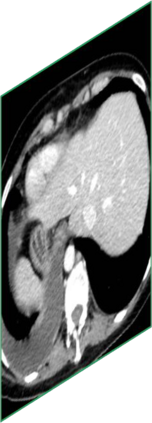

Due to the constraints of the imaging device and high cost in operation time, computer tomography (CT) scans are usually acquired with low intra-slice resolution. Improving the intra-slice resolution is beneficial to the disease diagnosis for both human experts and computer-aided systems. To this end, this paper builds a novel medical slice synthesis to increase the between-slice resolution. Considering that the ground-truth intermediate medical slices are always absent in clinical practice, we introduce the incremental cross-view mutual distillation strategy to accomplish this task in the self-supervised learning manner. Specifically, we model this problem from three different views: slice-wise interpolation from axial view and pixel-wise interpolation from coronal and sagittal views. Under this circumstance, the models learned from different views can distill valuable knowledge to guide the learning processes of each other. We can repeat this process to make the models synthesize intermediate slice data with increasing inter-slice resolution. To demonstrate the effectiveness of the proposed approach, we conduct comprehensive experiments on a large-scale CT dataset. Quantitative and qualitative comparison results show that our method outperforms state-of-the-art algorithms by clear margins.